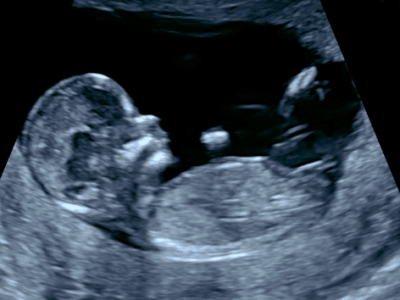

Accompagner votre maternité en douceur et harmonie

Les sages-femmes sont des professionnelles de la santé qui accompagnent les femmes tout au long de la grossesse, de l’accouchement et du post-partum. Elles offrent également des soins gynécologiques et des conseils en matière de contraception, santé reproductive et allaitement.